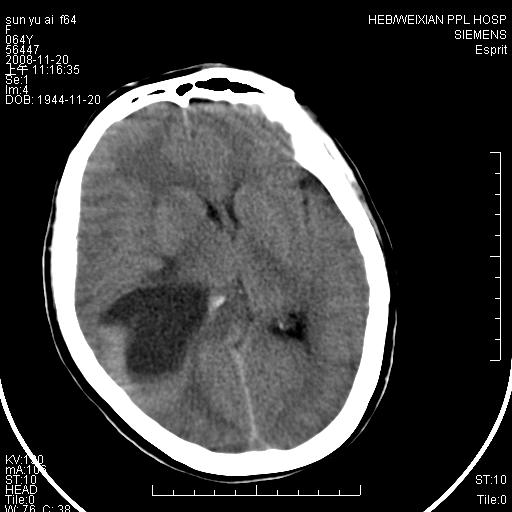

影像表现:侧脑室三角区附近可见以形态不规则的囊实性肿块,其中以囊性成分为主,实性成分为辅,边缘清晰,未见水肿,轻度占位效应,脉络丛钙化向内上移位,右侧脑室轻度扩大(也许体位所致),

1、右侧大脑半球囊实性占位病变,以囊性变为主,实性部分位于病变外后侧,周围无明显水肿,占位征象明显。

2、多考虑胶质瘤可能性大。

右颞顶叶囊实性占位,有壁结节。考虑间变性胶质瘤可能性大,建议增强进一步检查。

右颞顶叶囊实性占位,有壁结节,考虑胶质瘤可能性大,建议增强进一步检查。